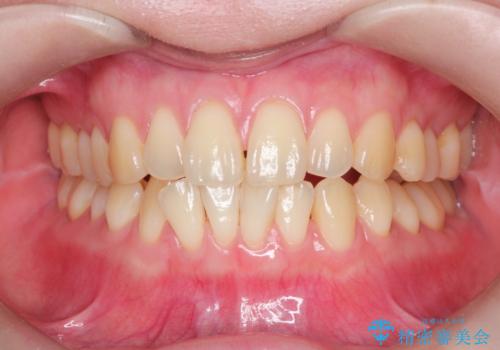

[ 前歯のねじれ・がたつき ] マウスピース矯正

![[ 前歯のねじれ・がたつき ] マウスピース矯正の症例 治療後](https://seimitsushinbi.jp/wp/wp-content/uploads/2024/02/e7a01485e4f4dd0da04705fde4cc34cc-500x350.jpg?v=1708502585)